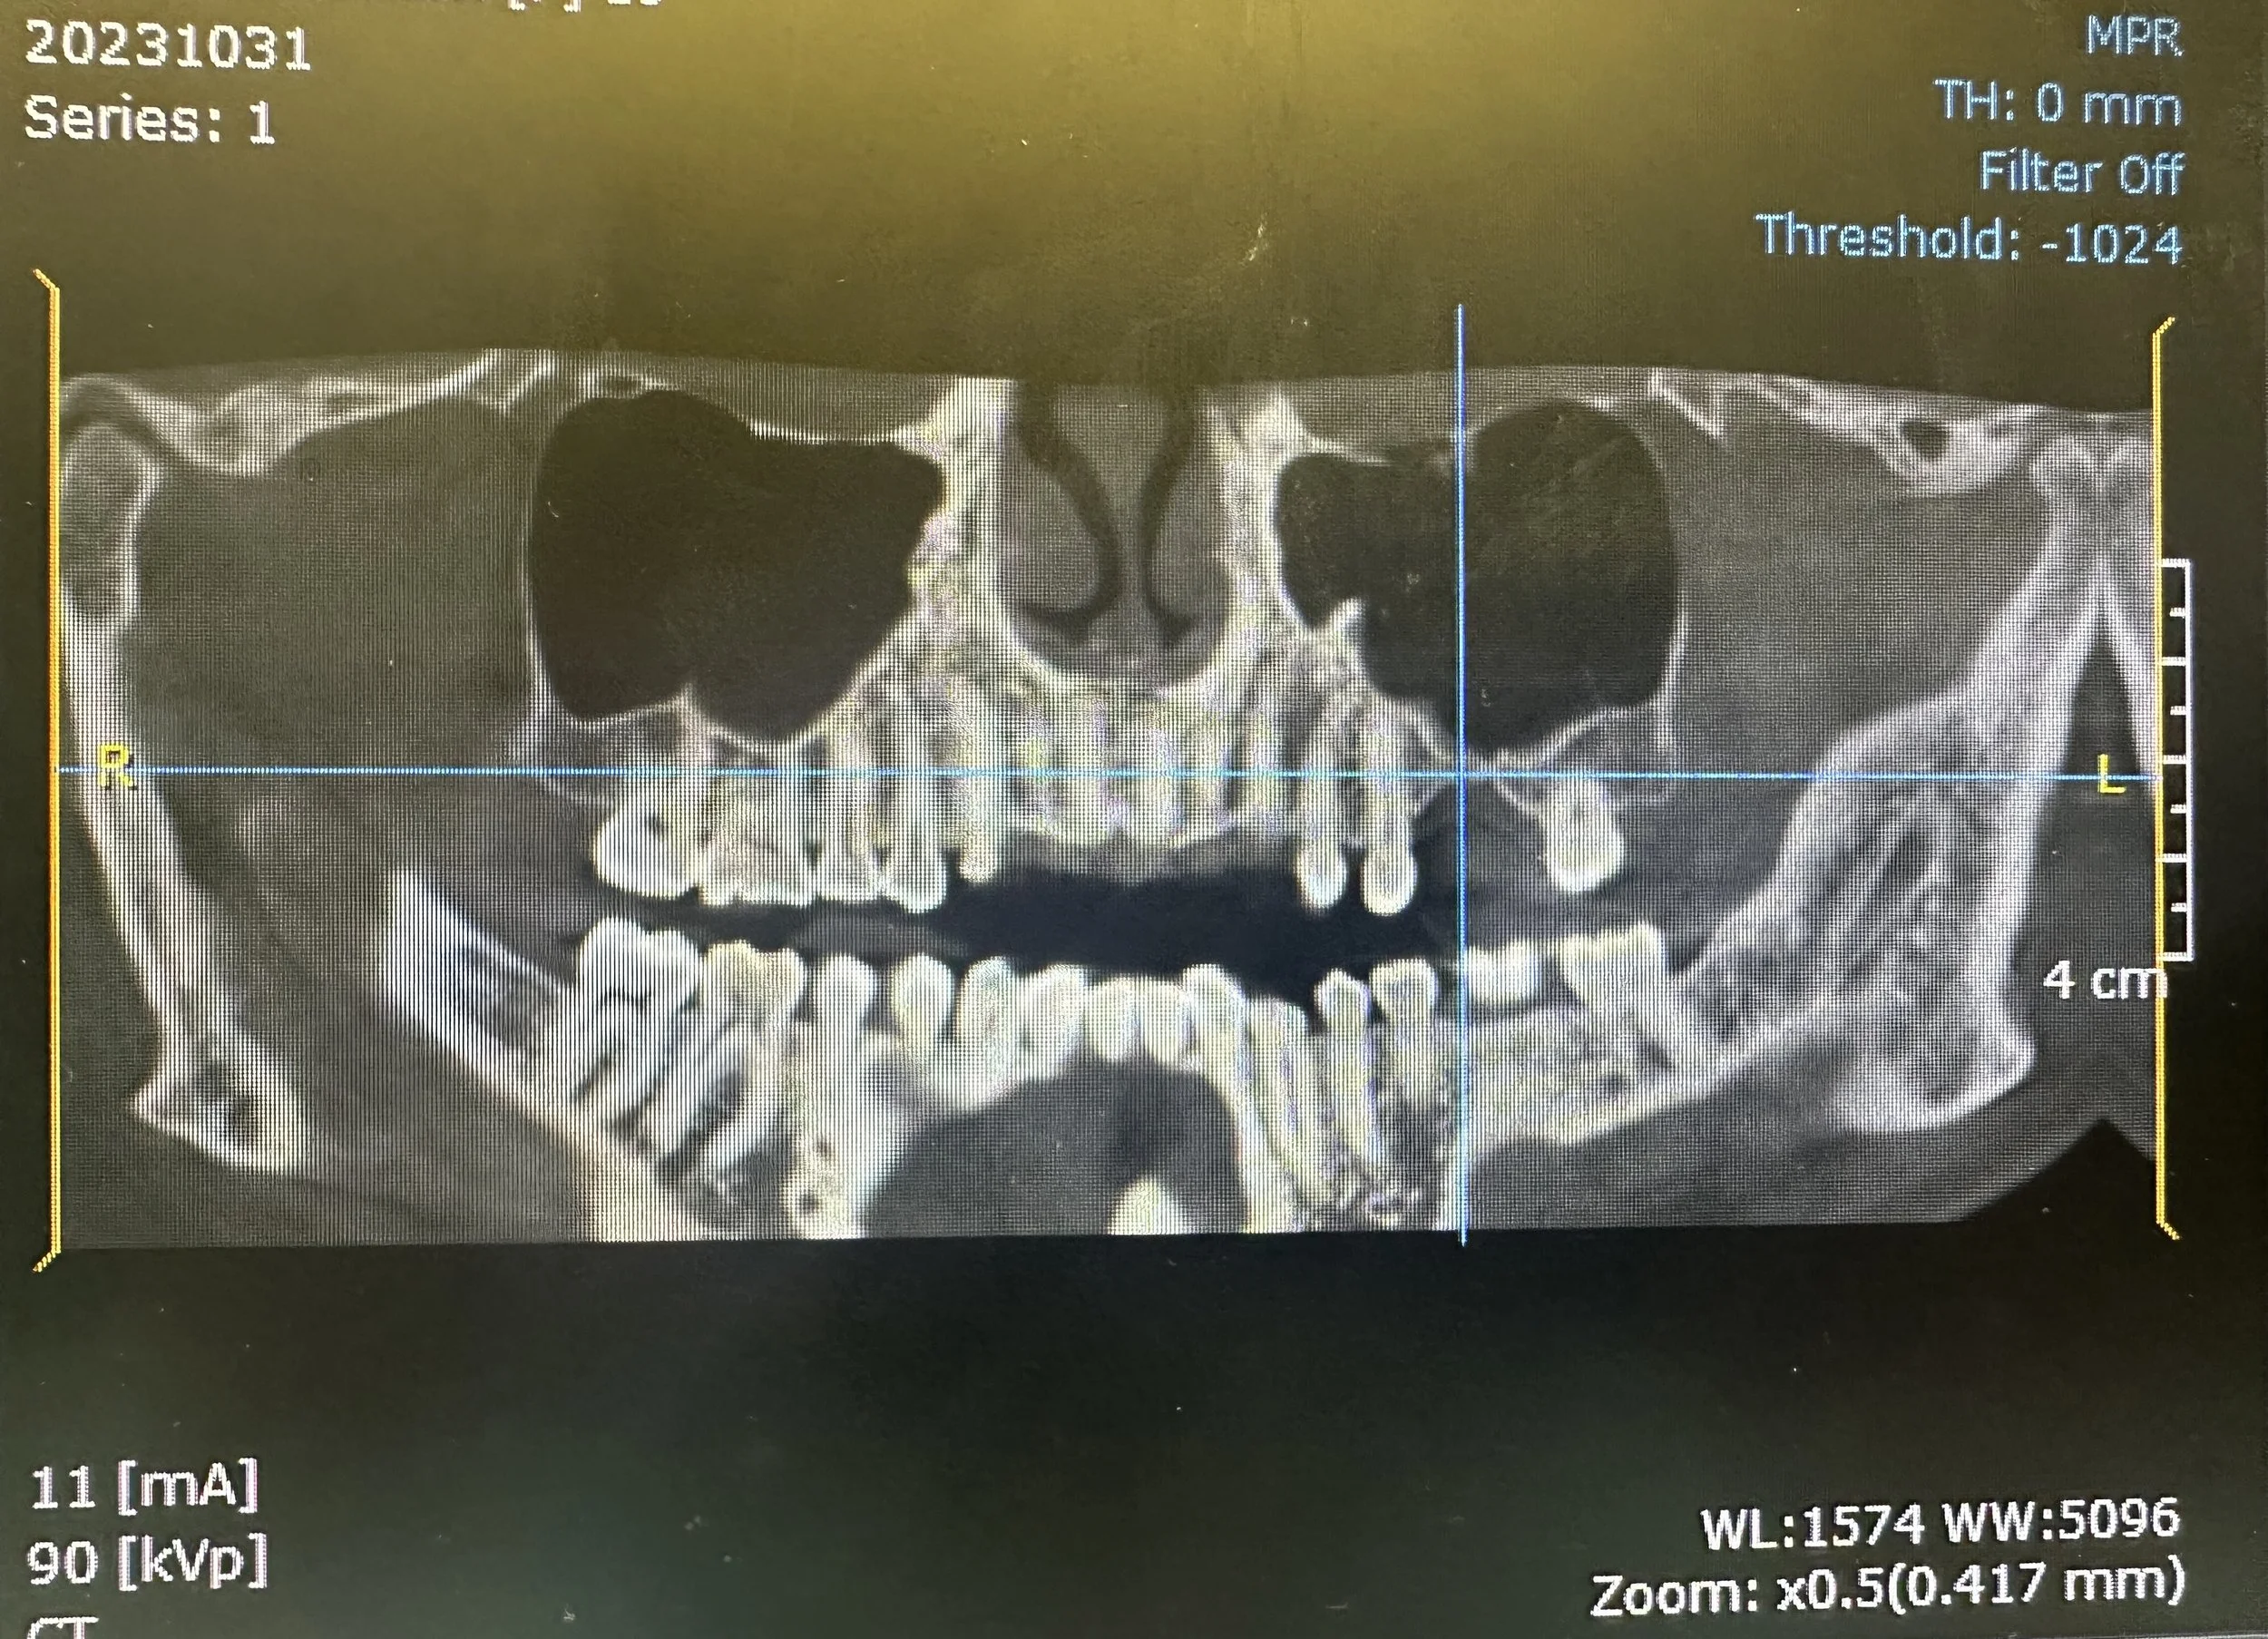

In this case, the patient presented with reduced vertical bone height in the upper left posterior region, making implant placement at site #14 unsuitable without prior augmentation. Advanced imaging confirmed the proximity of the maxillary sinus and the need for a staged surgical approach.

To restore the foundation for implant placement, a left maxillary lateral window sinus lift was performed. This technique allowed for controlled elevation of the sinus membrane and precise placement of bone graft material, increasing available bone volume while preserving surrounding anatomy.